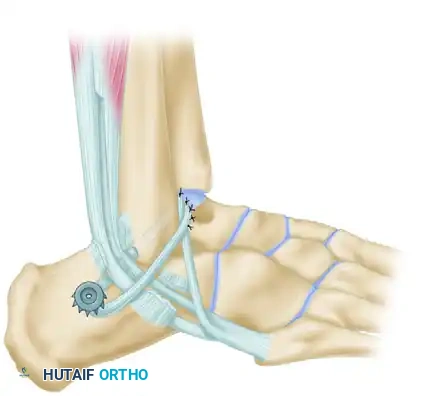

Step 5: Tendon Routing and Fibular Fixation

Pass the prepared tendon through the fibular hole from anterior to posterior.

Surgical Pearl: Hold the ankle in a strictly neutral position (0 degrees of dorsiflexion/plantarflexion and neutral inversion/eversion) during tensioning.

Suture the tendon to the robust periosteum over the anterior aspect of the fibula using non-absorbable sutures to establish the first point of fixation.

Step 6: Calcaneal Fixation

Pass the tendon deep to the peroneus longus tendon. The graft must now be secured to the lateral wall of the calcaneus to recreate the calcaneofibular ligament (CFL).

Drill a pilot hole into firm subchondral bone on the lateral aspect of the calcaneus. Select a 4-mm cancellous screw of appropriate length, paired with a spiked ligament washer.

Surgical Warning: Usually, a screw 30 mm long is sufficient. When measuring, add 3 to 4 mm to accommodate the thickness of the spiked washer. It is absolutely critical that the screw is not so long that it penetrates the medial calcaneal cortex, which could severely damage or tether the flexor hallucis longus (FHL) tendon or neurovascular bundle.

Pull the tendon inferior to the fibula to establish appropriate tension. Pass a No. 11 or No. 15 blade directly through the substance of the tendon to create a small slit. Insert the screw and washer through this slit. While maintaining strict traction on the tendon, advance the screw until the spiked washer gains firm, compressive purchase against the lateral calcaneal cortex. (If the lateral cortex is sclerotic, tapping may be required).

Step 7: Final Routing and Closure

Pass the remaining free end of the tendon (which is usually about 2 cm long) superficial to the peroneus longus tendon. Loop it back and attach it securely to itself at the tip of the fibula using multiple interrupted non-absorbable sutures.